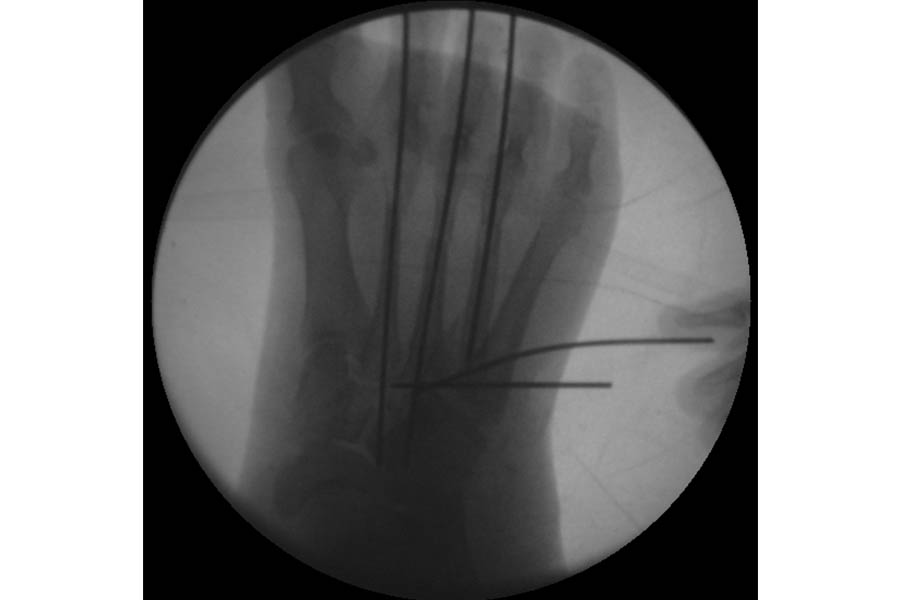

Trauma

Case 1